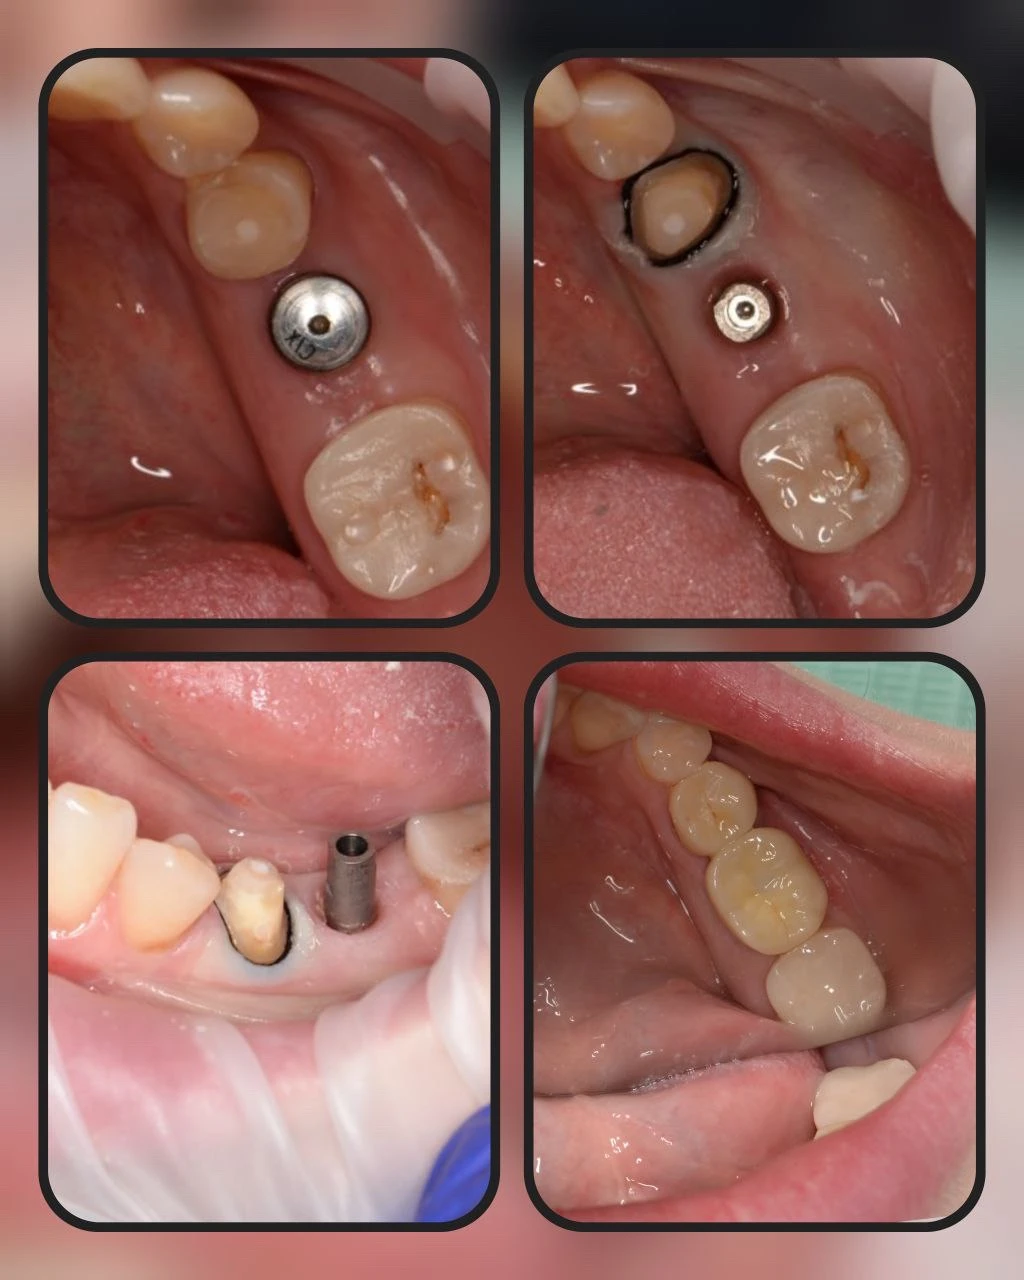

Цирконієва коронка на імпланті 46

Цирконієва коронка 45 та цирконієва коронка 46 на імпланті

Цирконієва коронка 35 та цирконієва коронка 36 на імпланті